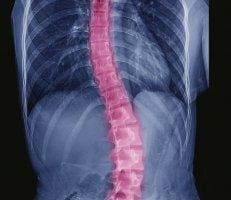

آلام الظهر لدى المراهقين المصابين باعوجاج العمود الفقري: الأسباب، التشخيص، وأفضل طرق العلاج

يعاني العديد من المراهقين المصابين باعوجاج العمود الفقري (Adolescent Idiopathic Scoliosis – AIS) من آلام في الظهر، وهي واحدة من أكثر المشاكل شيوعًا التي تؤثر على جودة حياتهم اليومية. على الرغم من أن هذا النوع من الاعوجاج غالبًا ما يُعتبر بدون أعراض جسدية كبيرة، إلا أن بعض المراهقين قد يعانون من آلام مزمنة أو شعور بعدم الراحة، خصوصًا مع زيادة شدة الانحناء أو خلال فترات النمو السريع.

آلام الظهر في هذه الفئة غالبًا ما تكون ناتجة عن تغييرات ميكانيكية في توزيع القوى على العضلات والفقرات والأربطة. عندما ينحني العمود الفقري بشكل جانبي، يحدث ضغط غير متساوٍ على العضلات الخلفية والأمامية، ما قد يؤدي إلى: